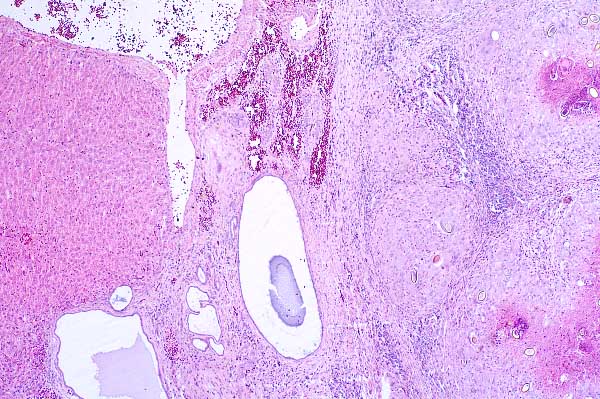

| 4x   |   Hematoxylin and Eosin | ||||

There is multifocal hemorrhage at the interface between the normal parenchyma and the granulomas.